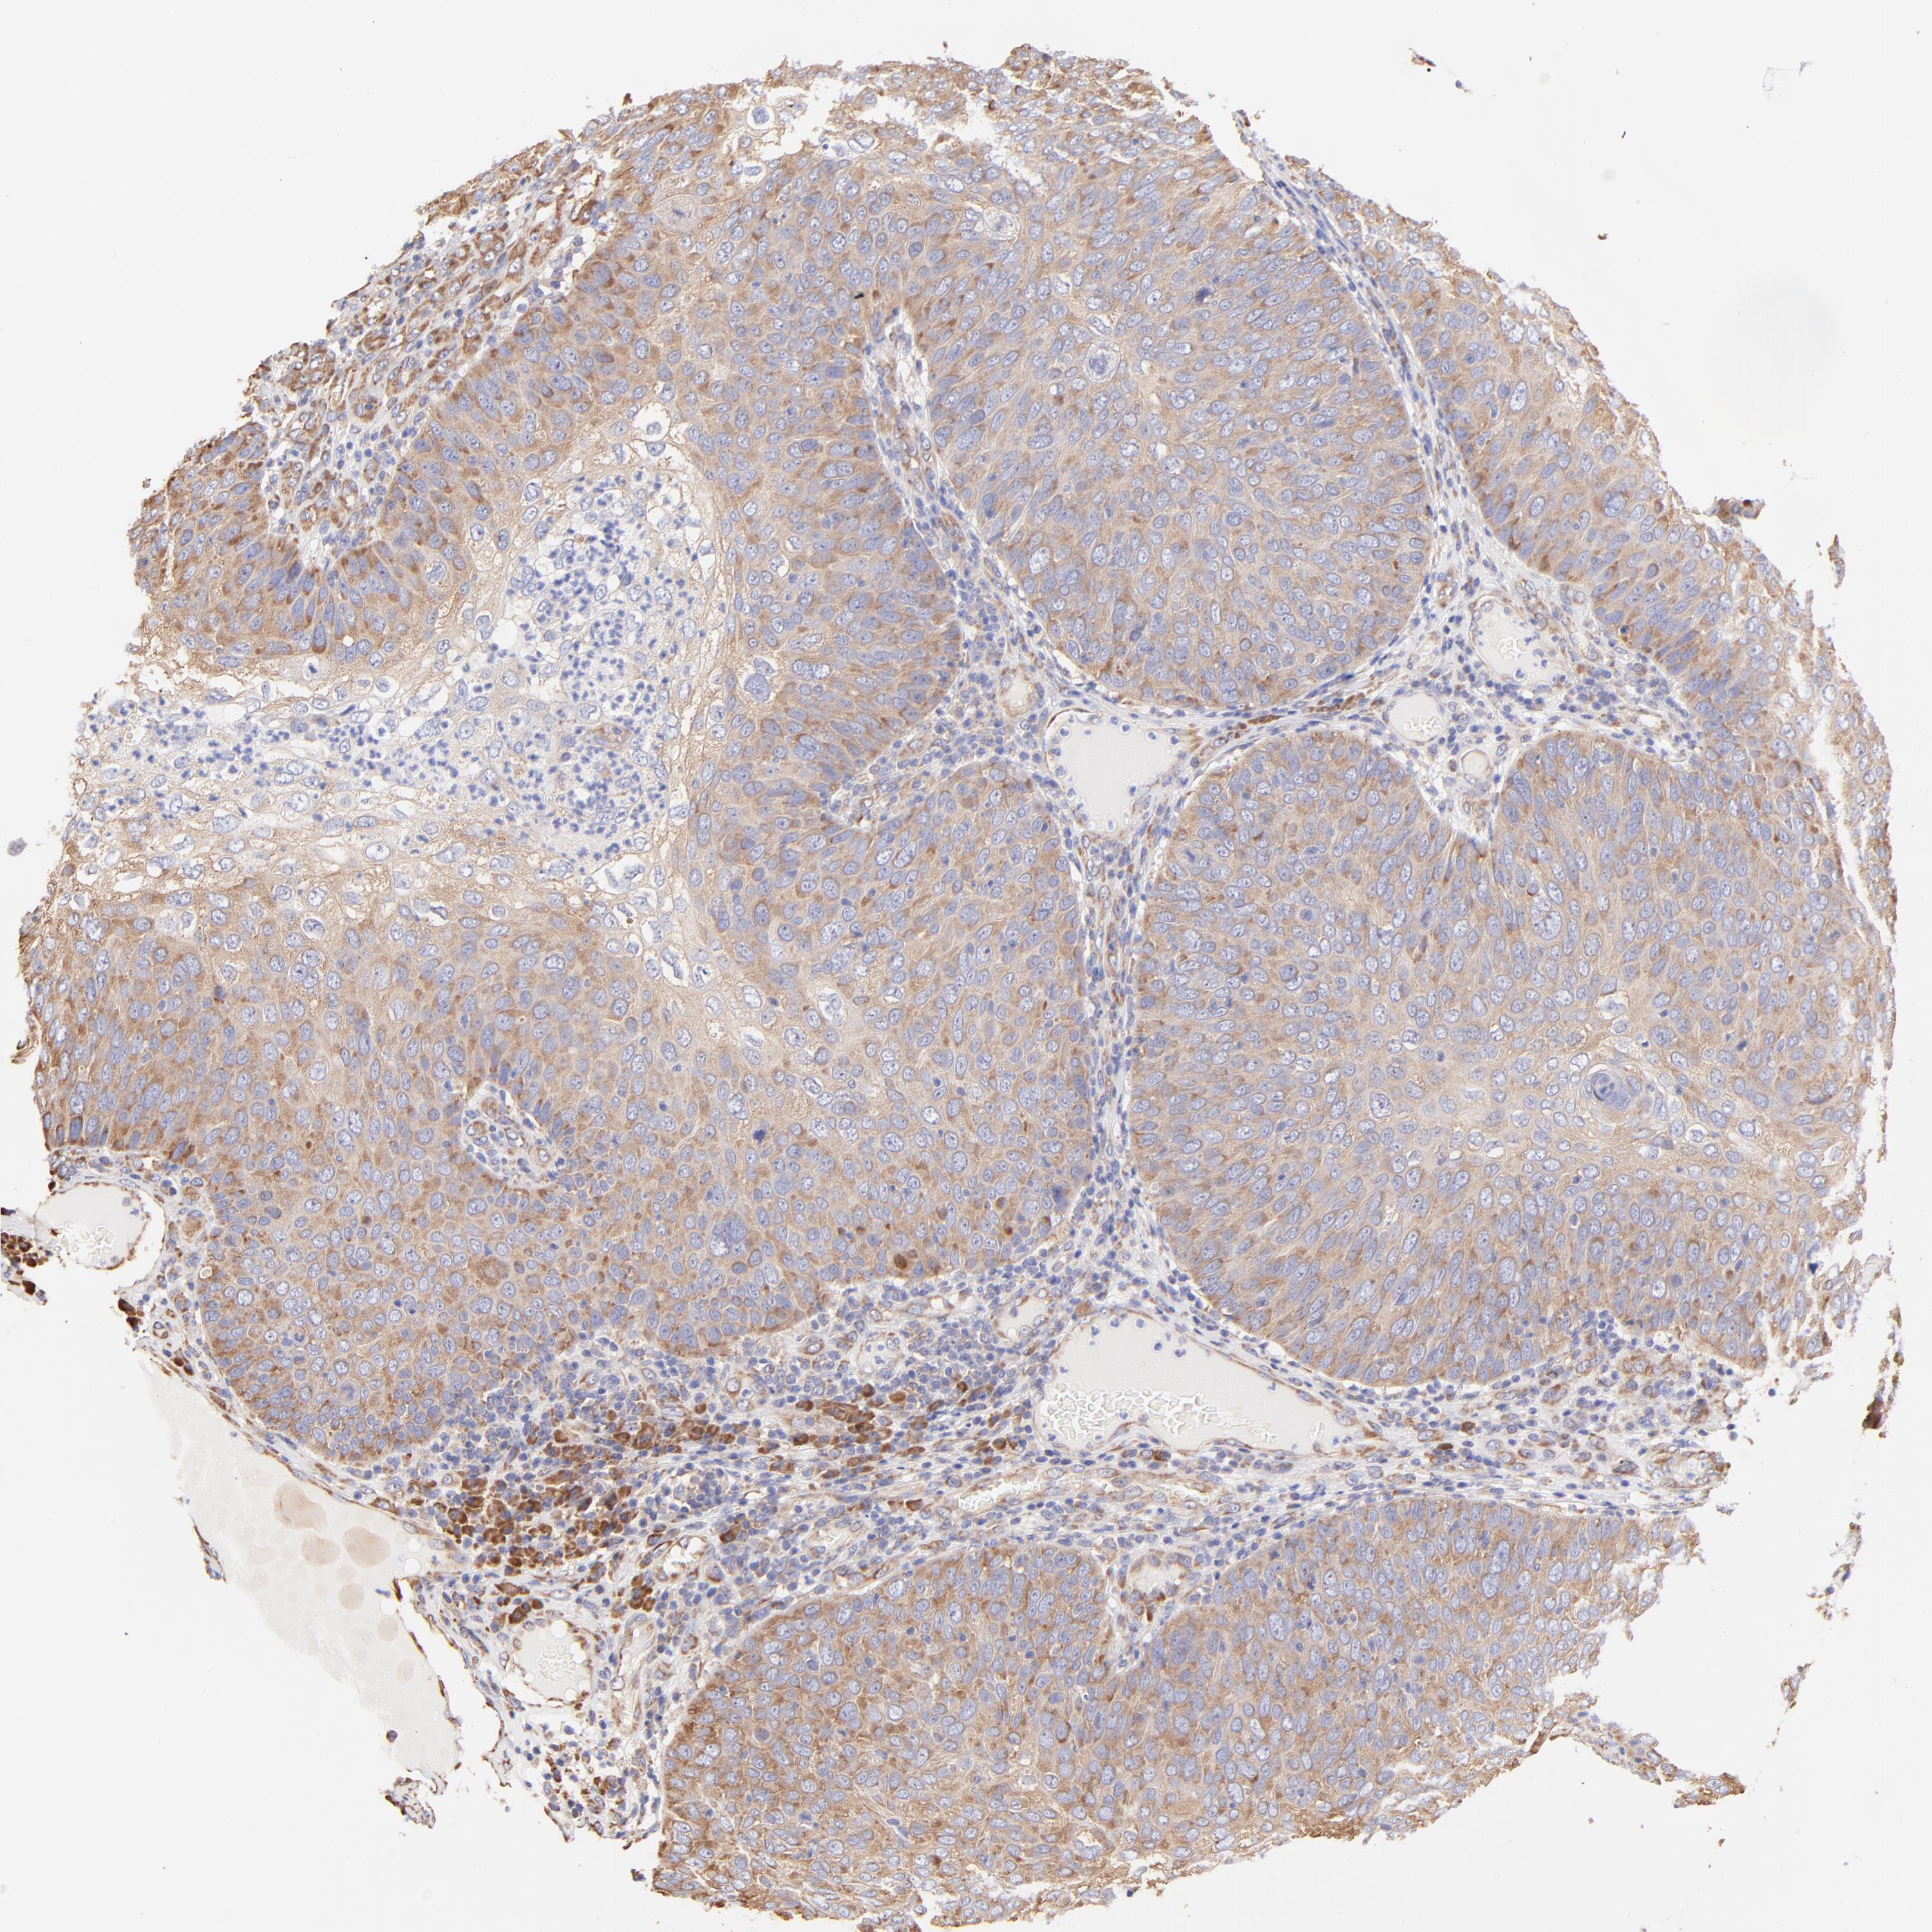

SKIN CANCER - Protein expressioni

A mouse-over function shows sample information and annotation data. Click on an image to view it in a full screen mode. Samples can be filtered based on level of antibody staining by selecting one or several of the following categories: high, medium, low and not detected. The assay and annotation is described here.

Antibody stainingi

Antibody staining in the annotated cell types in the current human tissue is reported as not detected, low, medium, or high, based on conventional immunohistochemistry profiling in selected tissues. This score is based on the combination of the staining intensity and fraction of stained cells.

Each image is clickable and will lead to virtual microscopy that enables deeper exploration of all samples and also displays staining intensity scores, fraction scores and subcellular localization as well as patient and tissue information for each sample.

Antibody HPA002651

Staining

High

Medium

Low

Not detected

Intensity

Strong

Moderate

Weak

Negative

Quantity

>75%

75%-25%

<25%

None

Location

Nuclear

Cytoplasmic/membranous

Cytoplasmic/membranous,nuclear

Squamous cell carcinoma, NOS

Basal cell carcinoma